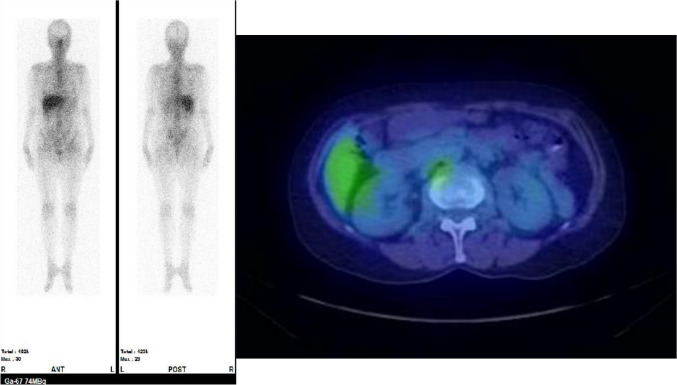

To date, the treatment strategy and long-term prognosis of acute kidney injury (AKI) after taking Benikoji CholesteHelp®, a red yeast rice supplement, remains unclear. We present three cases wherein renal dysfunction improved within a few months of supplement discontinuation, without immunosuppressive therapy. Case 1: A 59-year-old woman with a history of hypertension, treated with telmisartan (serum creatinine [sCr]: 0.65 mg/dL; estimated glomerular filtration rate [eGFR]: 71.3 mL/min/1.73 m2) and Benikoji CholesteHelp® for 7 months, developed Fanconi syndrome (FS) and severe renal impairment (sCr: 2.32 mg/dL; eGFR: 17.7 mL/min/1.73 m2). Renal biopsy and gallium-67 scintigraphy revealed no active drug-induced interstitial nephritis. Her condition improved significantly after supplement discontinuation. Her renal function gradually improved, with 3-month follow-up sCr and eGFR values of 0.96 mg/dL and 46.5 mL/min/1.73 m2, respectively; however, these were still worse than the pre-onset values. Case 2: A 48-year-old man had mild renal dysfunction (sCr: 1.12 mg/dL; eGFR: 56.76 mL/min/1.73 m2) after taking Benikoji CholesteHelp® for approximately 2 years; this was reversed upon supplement discontinuation. Case 3: A 47-year-old man with FS and mild renal dysfunction (sCr: 1.09 mg/dL; eGFR: 58.5 mL/min/1.73 m2) after taking Benikoji CholesteHelp® for approximately 4 months, showed notable improvement in FS after supplement discontinuation; however, the mild renal dysfunction persisted. The primary intervention in all cases was immediate supplement discontinuation, leading to rapid improvement in renal function, without need for immunosuppressive therapy. These findings increase our understanding of renal impairment caused by red yeast rice, with improvement after withdrawal, sometimes after several months.